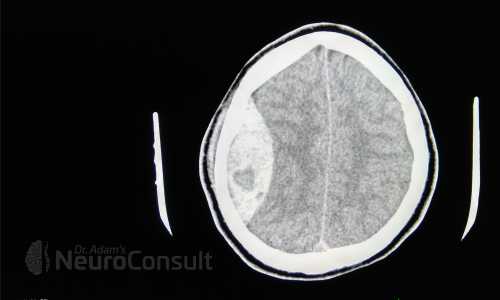

My Cases Studies & Work